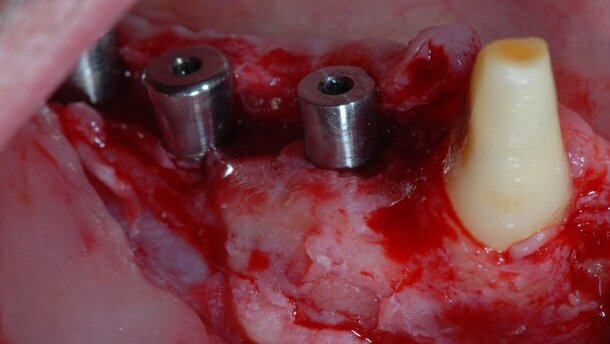

Un paziente, in buone condizioni di salute generale, non fumatore, è stato sottoposto a intervento chirurgico per l’inserzione di tre impianti osteointegrati (SK3 Shakleton), in zona primo e secondo premolare e primo molare mandibolare di destra. Si è seguito il protocollo chirurgico, indicato per gli aumenti di cresta verticale in GBR13,14. All’esame obiettivo si osserva un’architettura ossea caratterizzata da concavità, di entità moderata, in corrispondenza degli impianti inseriti (Fig. 1). La riduzione di spessore orizzontale porta all’esposizione di una spira in corrispondenza dell’impianto intermedio, e a perdita di continuità della cresta ossea alveolare in corrispondenza dell’impianto, in posizione più mesiale (Fig. 1).

Con una fresa cilindrica di diametro uguale a quello della sutura PDS II, montata su un manipolo a bassa velocità, si creano numerose perforazioni ossee della corticale per accedere alle sottostanti cavità midollari, al fine di stimolare la partecipazione di cellule mesenchimali (Fig. 1).

Per creare un effetto “a cupola”, si è utilizzato un filo di sutura assorbibile PDS II (polidioxanone, Ethicon/Johnson & Johnson) (Figg. 2, 3). Due segmenti di PDS II, precedentemente tagliati della lunghezza desiderata, vengono inseriti in quattro dei fori eseguiti, per trattenere in situ i fili di sutura (Figg. 2, 3), creando così un effetto a cupola (Figg. 2, 3).